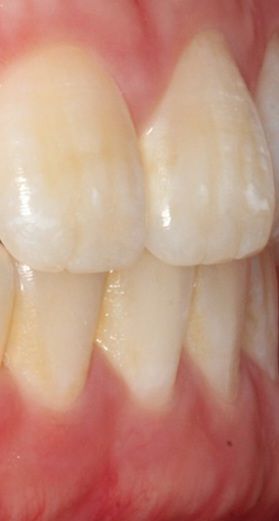

윗니가 아랫니 포개기는 하는데 겨우포개는 느낌이듭니다 윗니가 앞으로 나온게 적은건지 아랫니가 많이 나온걸까요?

이정도만 포개도 상관없는축에 속하나요?

사진상으로 보았을 때는 치축의 각도가 정상 범주에서 벗어나는 것이 맞습니다. 다만 치열이 고르고 특별히 불편감이 없다면 치료의 대상은 아닙니다. 오히려 현재 골격에서 아래 위 치아의 치열 각도를 바꾸게 되면 심미적으로 더 이상해보일 수 있으므로 정확한 교정적 평가 이후에 교정을 하는 것이 필요하며 교정 이후에 오히려 어색해보일 수도 있어 보입니다.

윗니가 아랫니를 수직적으로 2-3mm덮는게 정상입니다.

사진상으로 큰 문제는 없어보입니다.

이상적인 피개교합은 2mm입니다.

사진상으로는 크게 이상은 없어 보입니다. 윗니가 아랫니를 덮는정도면 몇mm이며, 너무 깊게 물리거나 끝이 물리는게 더 안좋은 상태입니다. 크게 걱정은 안하셔도될것같습니다.